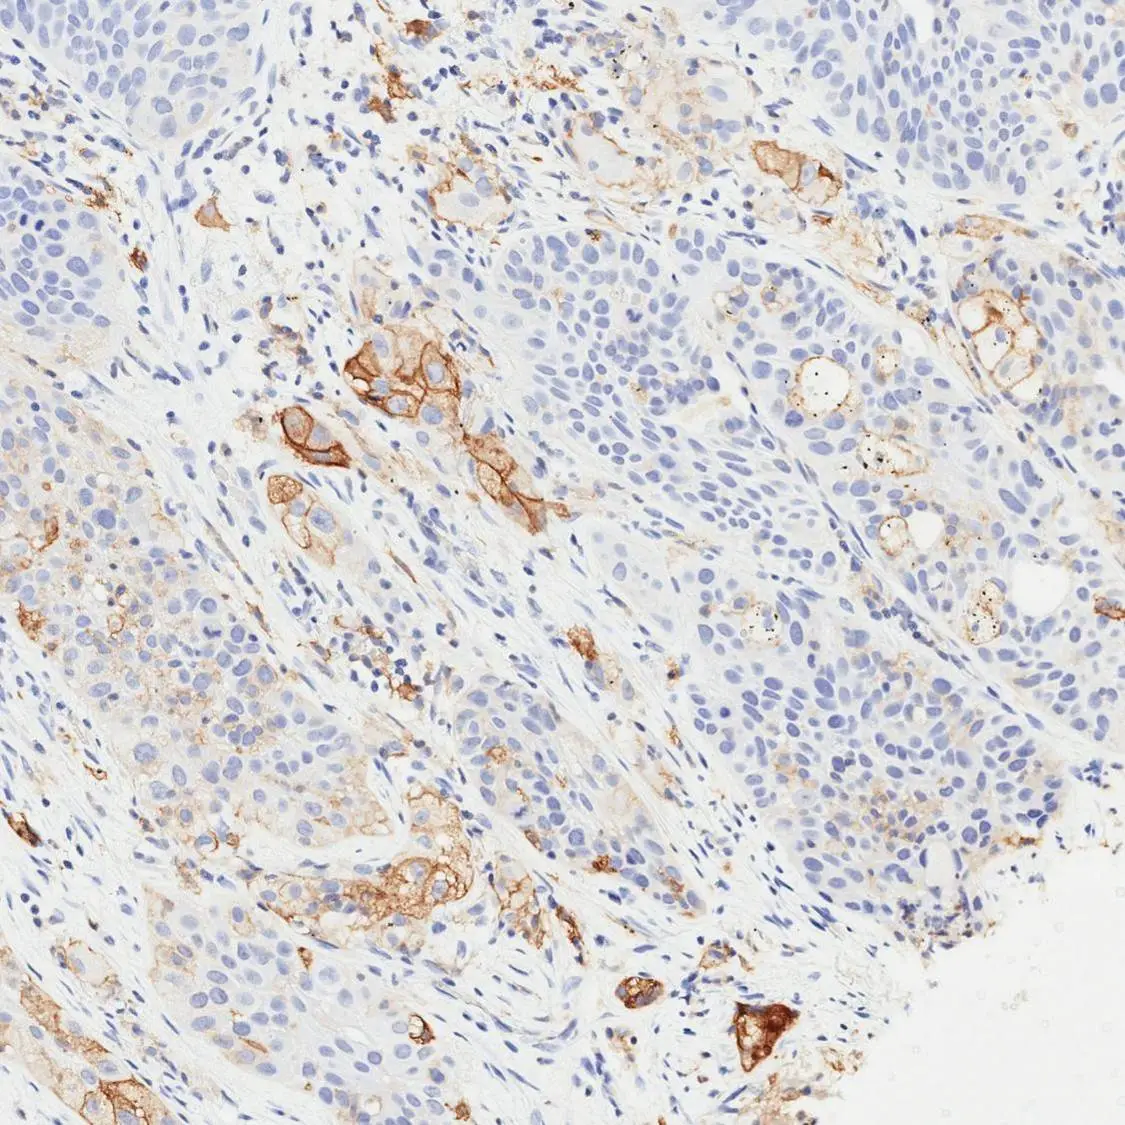

IHC-P analysis of human esophageal adenocarcinoma (EAC) tissue using GTX639925 PD-L1 antibody [H302] HistoMAX™.

PD-L1 negative esophageal adenocarcinoma showing intense PD-L1 positivity of tumor adjacent macrophages.